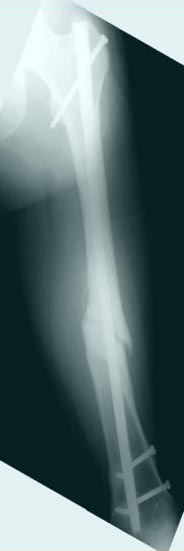

Из истории болезни: два года назад проперирован по поводу 3А открытого перелома бедра, травма на работе в результате "стена упала на него".Сопутствующая травма: Закрытая травма черепа, перелом голеностопного сустава (прооперериван) и перелом плеча (консервативное лечение)

Лечение бедра - ургентное оперативное лечение антеградным с минимально рассверливанием, фиксацией с минимальным диаметром штифта и плюс irrigation and debridment и с закрытием поперечной до 10 см раны на уровне перелома в день поступления.

После трех дней начались выделения из ран которые промывалась в палате и рана постепенно закрылась в течение нескольких месяцев. Эмпирически получал 6 недельний курс антибиотика Vancomycin внутривенно.

Снимки представлены: 1 мес; 3 мес; 1 год; 2 года, предоперационные и ротационная КТ грамма